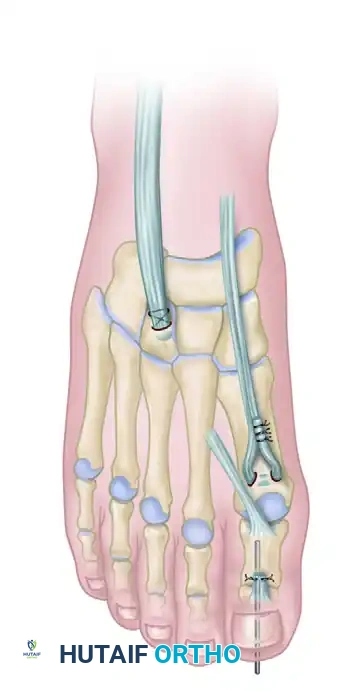

Gould routinely added the Jones procedure to increase and maintain the correction of the first ray. The extensor hallucis longus (EHL) is detached from the distal phalanx and transferred to the neck of the first metatarsal.

This transfer removes the deforming dorsiflexion force on the toe (which contributes to clawing) and converts the EHL into a dynamic dorsiflexor of the first metatarsal, counteracting the overpowering peroneus longus. The interphalangeal joint of the hallux is subsequently arthrodesed to prevent a drop-toe deformity.

The Hibbs procedure involves the detachment of the extensor digitorum longus (EDL) tendons from the lesser toes. The proximal stumps of the EDL tendons are then tenodesed together and transferred into the middle cuneiform (or the base of the third metatarsal) via a bone tunnel or suture anchor.

Completed Hibbs and Jones procedures. The EHL is transferred to the first metatarsal, and the EDL tendons are transferred to the middle cuneiform, providing dynamic dorsiflexion to the midfoot.

This transfer serves a dual purpose: it eliminates the hyperextension force at the metatarsophalangeal (MTP) joints (allowing the toes to drop into a corrected position) and recruits the EDL to assist in global ankle and midfoot dorsiflexion.